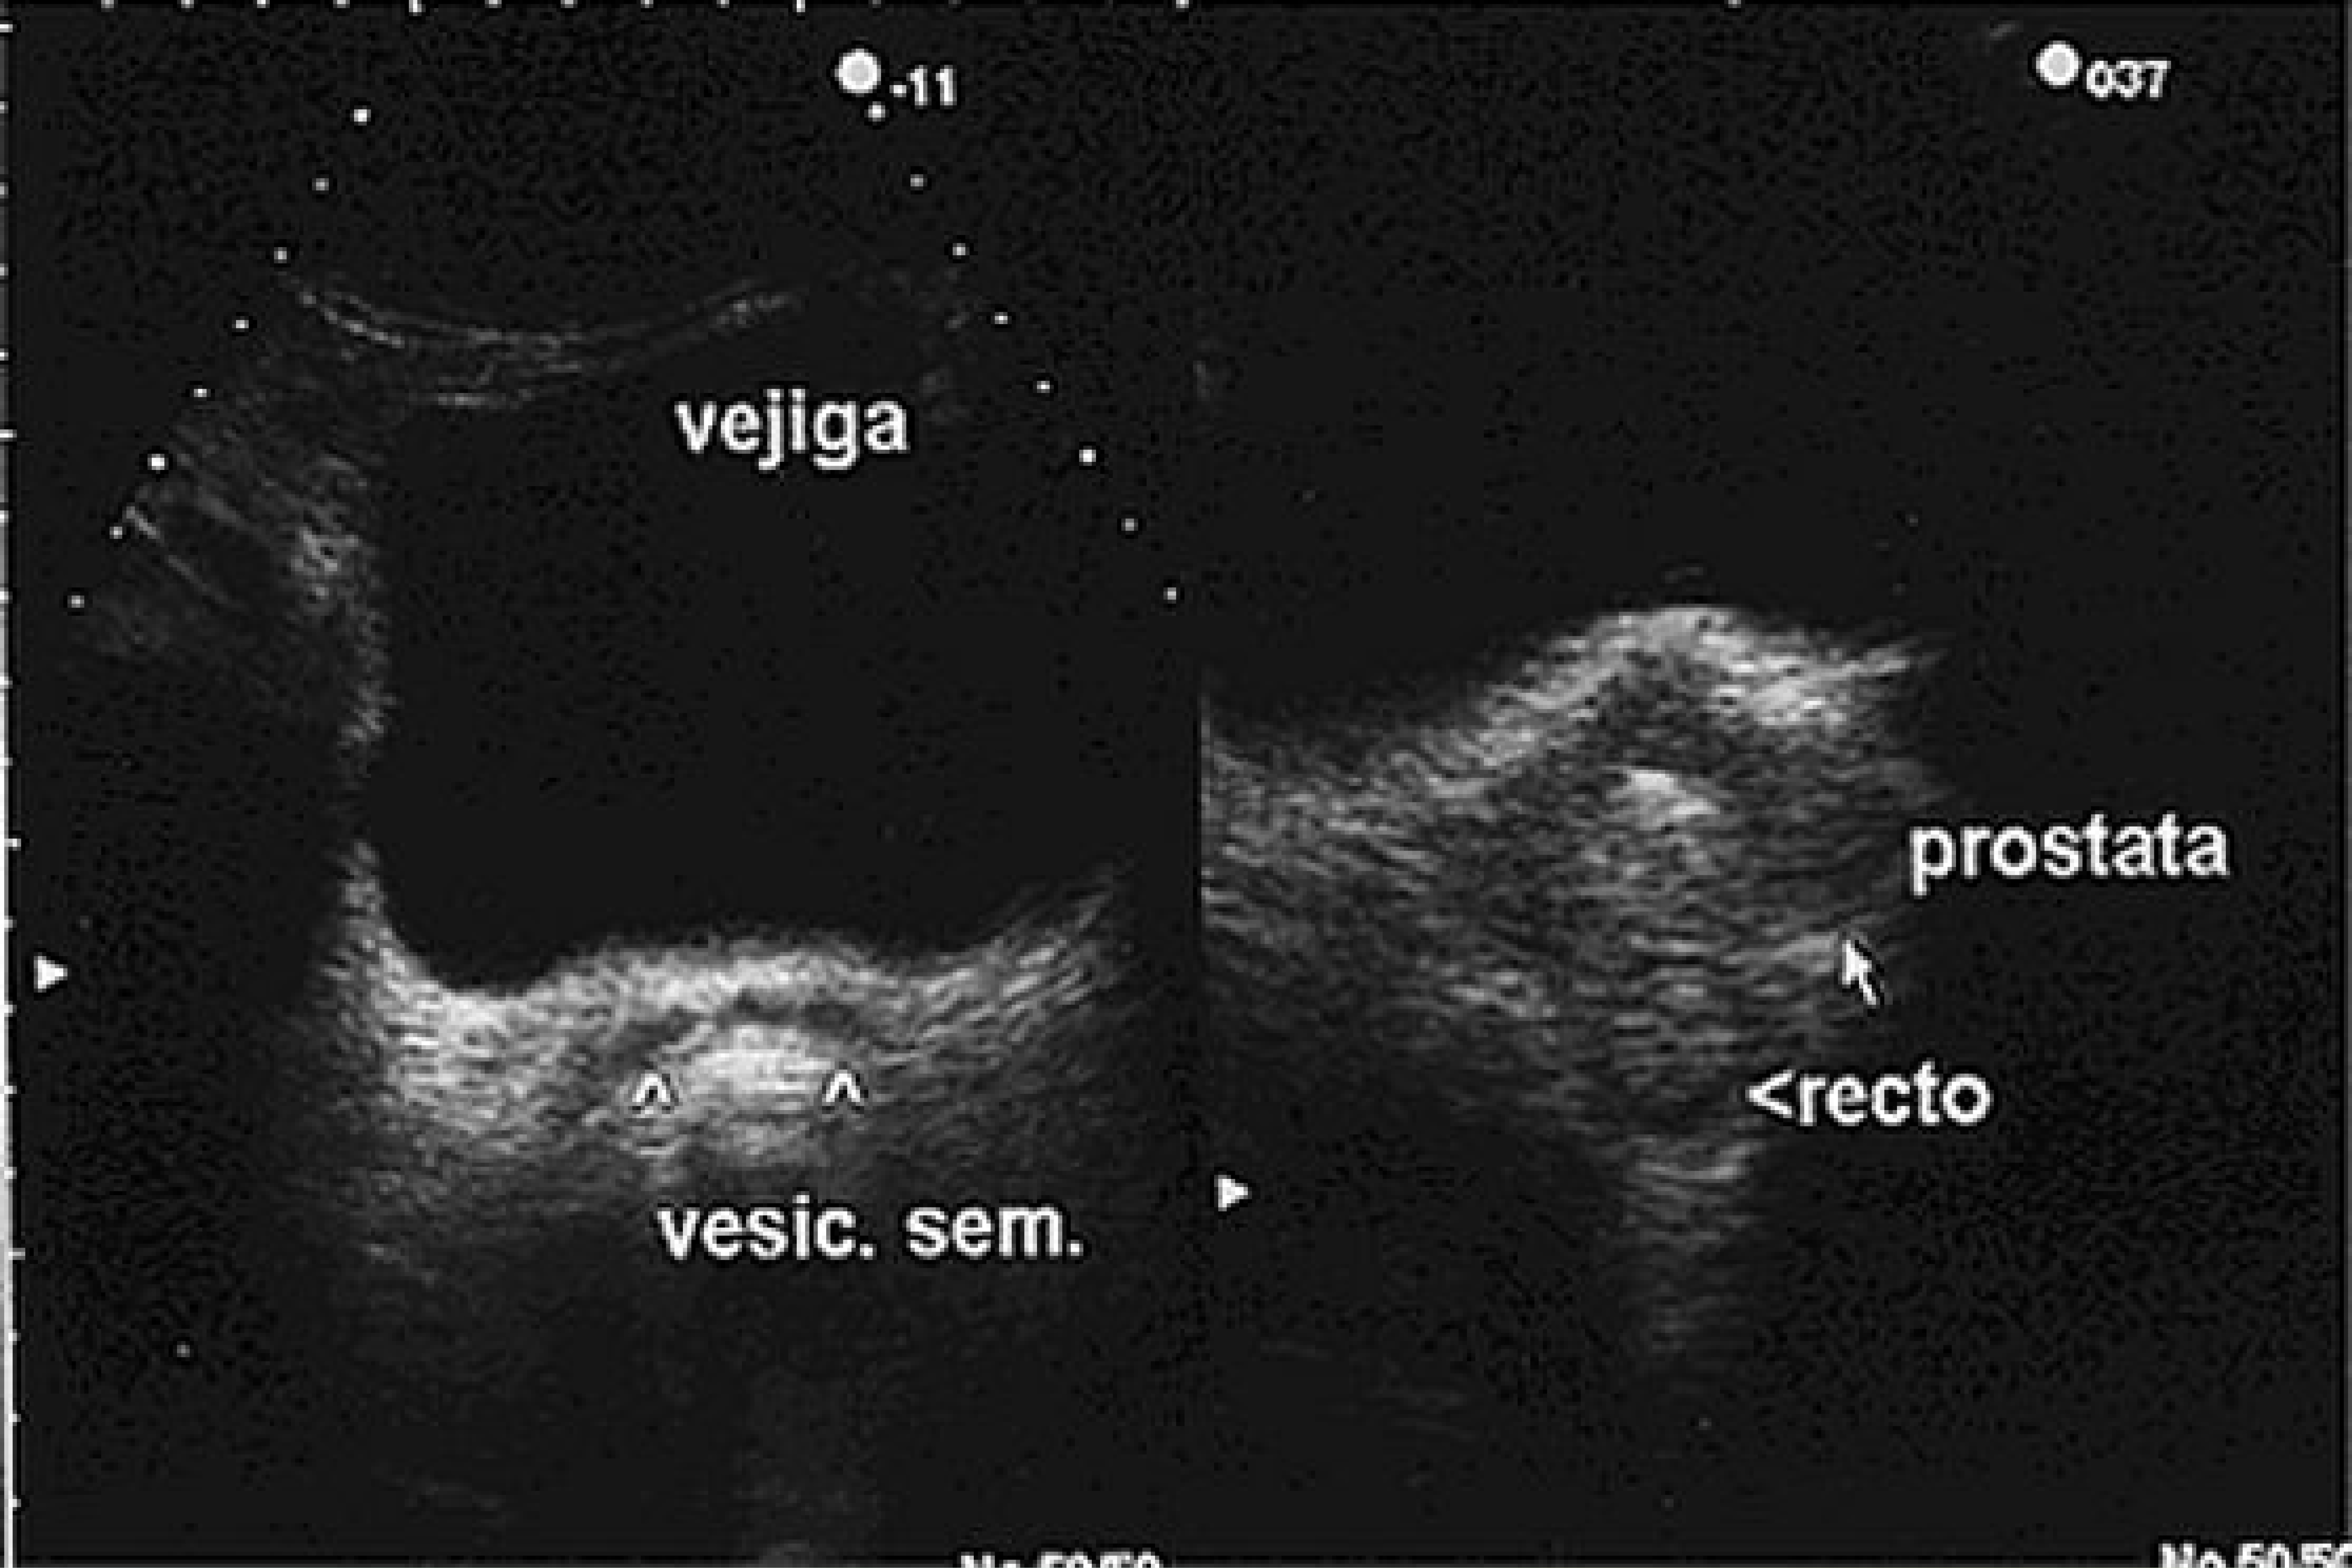

Valor diagnóstico del ultrasonido transrectal en el cáncer de próstata